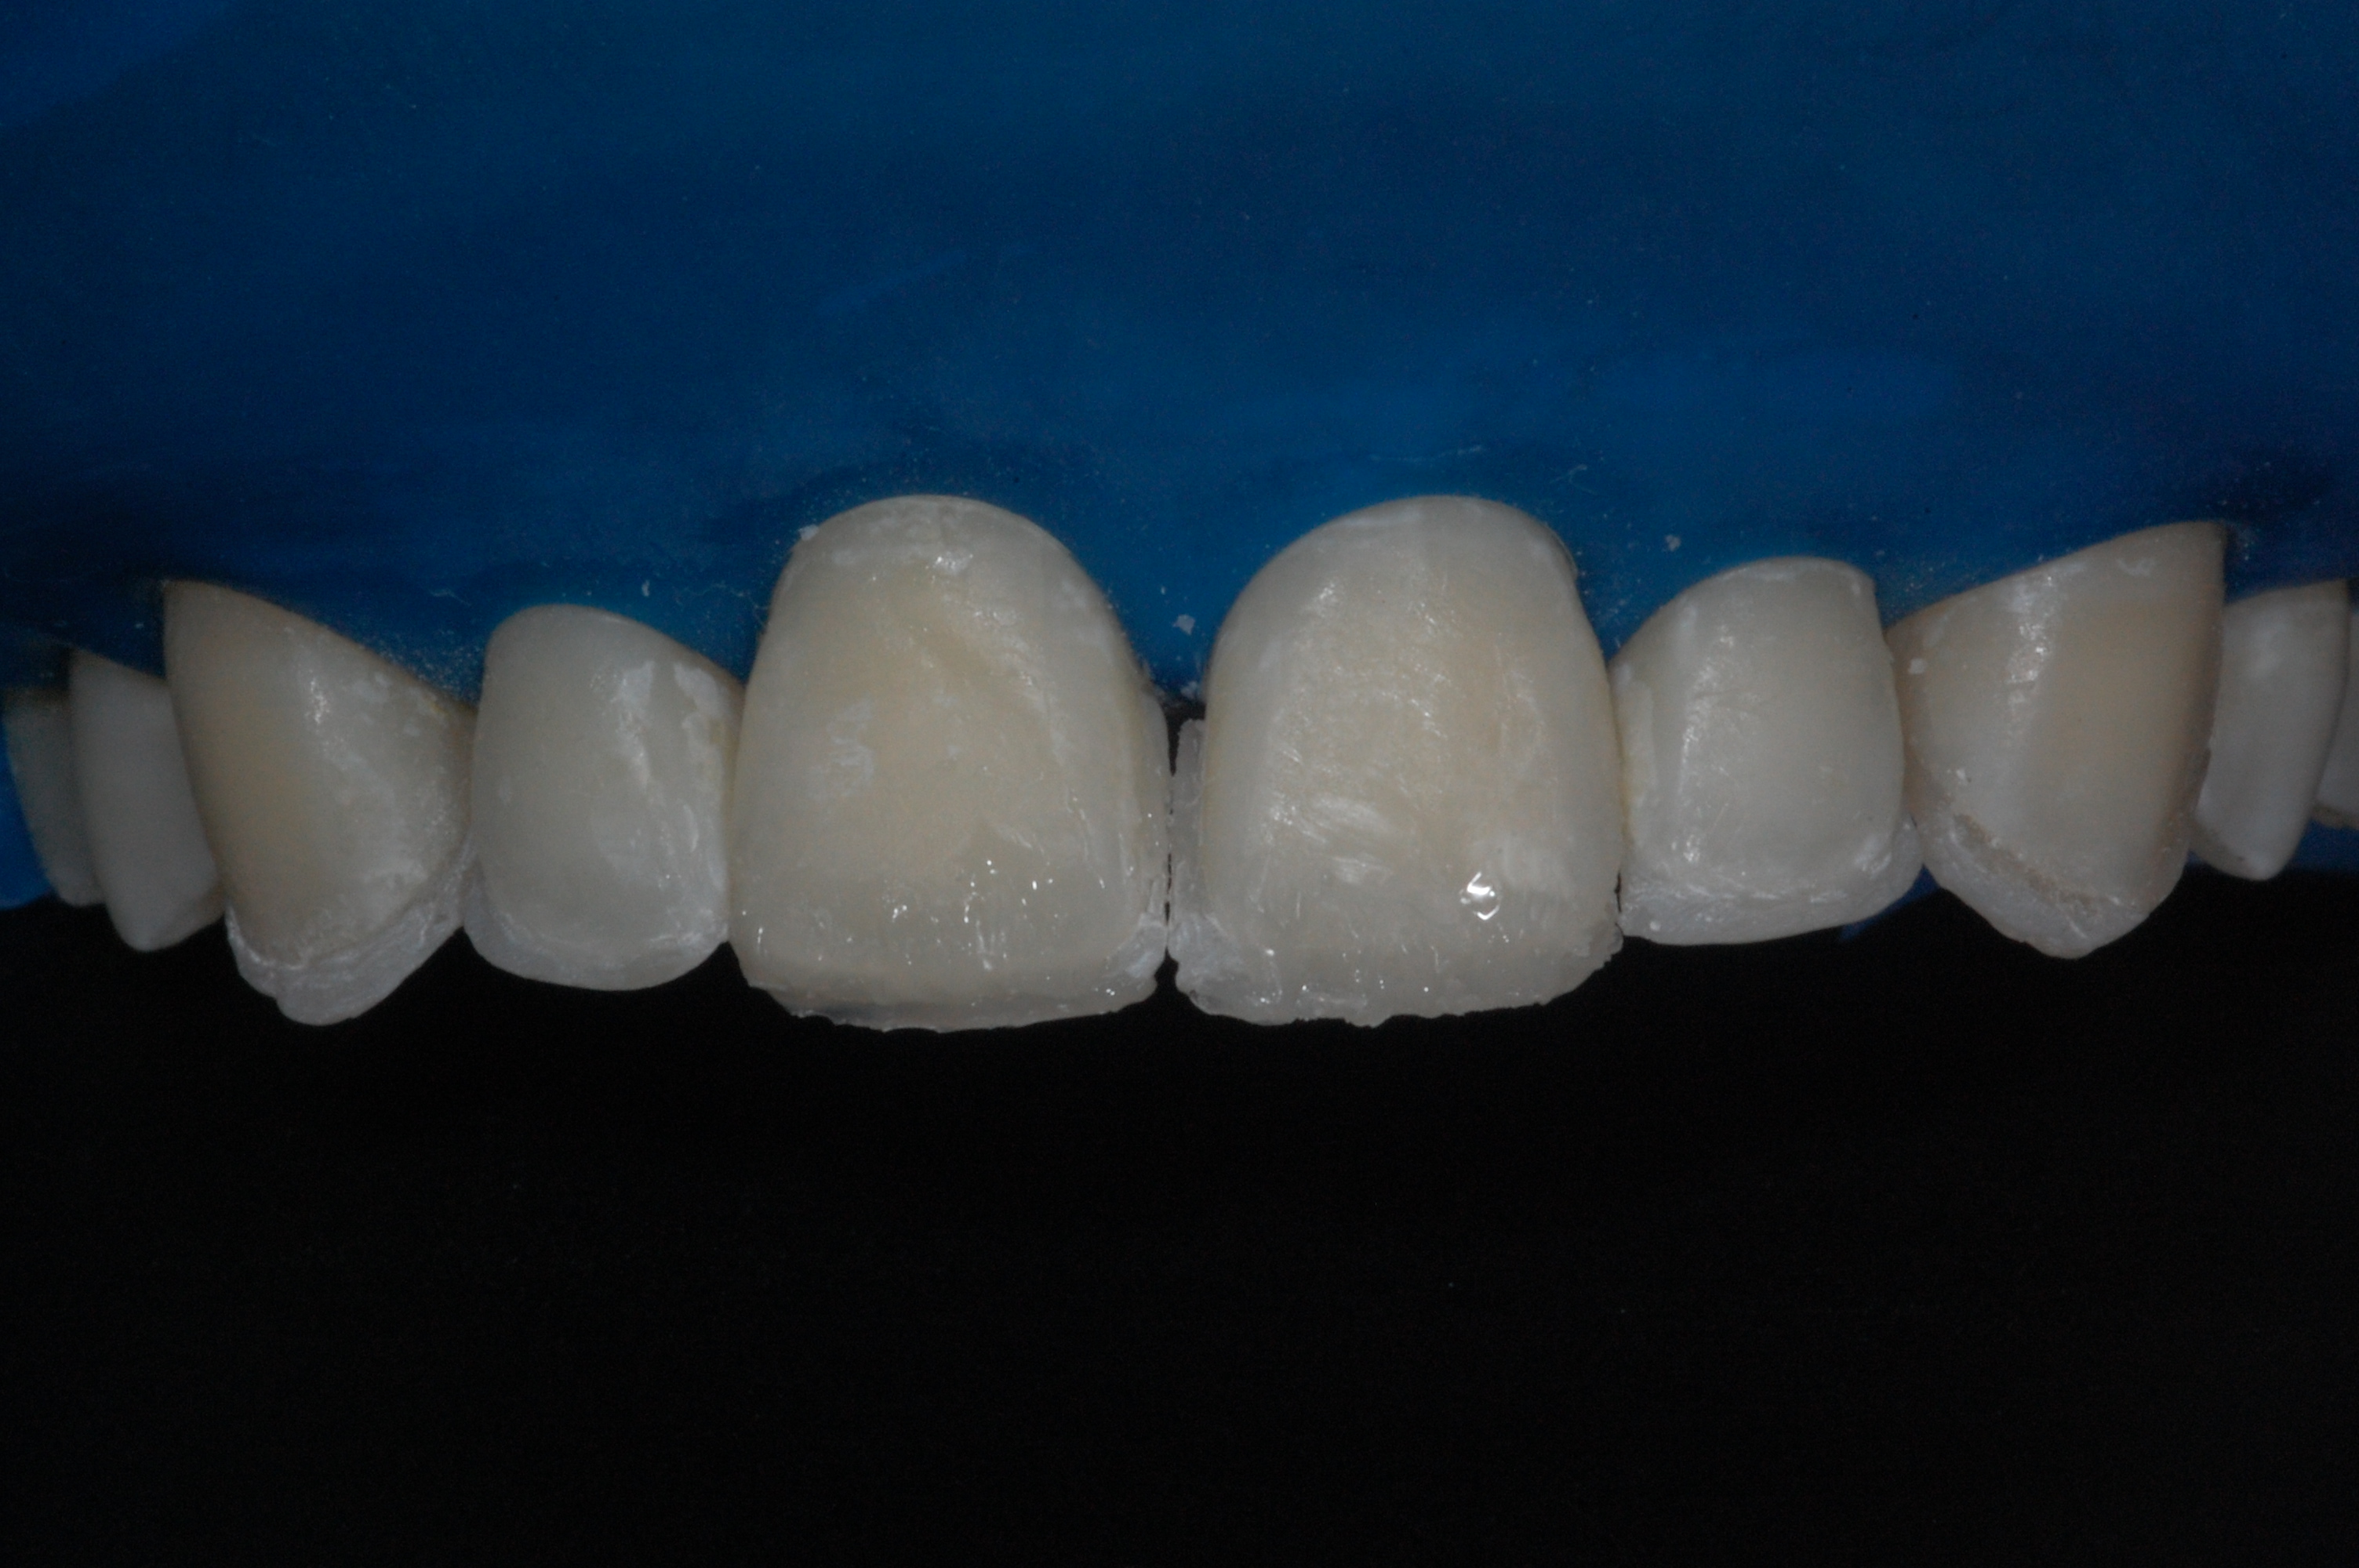

The presence of diastema, between anterior teeth, distorts a pleasing smile by concentrating the observer’s attention on the spaces. The patient’s needs and expectations must be considered in the process of treatment planning to ensure satisfaction with the treatment outcomes. There are many forms of therapy that can be used for diastema closure. A carefully developed diagnosis, which includes a determination of the causal elements and advanced treatment planning, allows the most appropriate treatment to be selected for each case. The aim of this paper is present a multidisciplinary approach as a solution to multiple diastemas in the anterior region using gingival tissue recontouring and direct adhesive restorations, with minimum wear of the dental structure, after the orthodontic intervention discussing the minimal intervention to obtain imperceptive and aesthetic final restoration. Thirty-six months after the treatment was carried out, the final aesthetic was maintained with all dental element details and gingival tissue harmony, without recurrence of periodontal pockets and the preservation of the tooth color and shape.